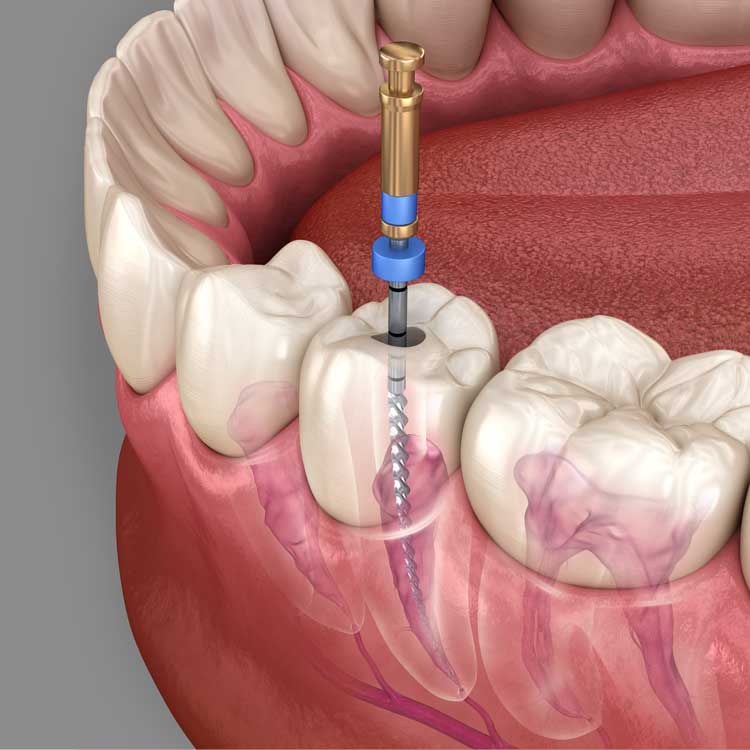

השתלות דנטליות

השתלות דנטליות הן תהליך רפואי שבו משתילים שתלים במקום שן חסרה או פגומה. השתלים הם רכיבים ממתכת (בדרך כלל טיטניום), אשר מוחדרים לעצם הלסת כדי לשמש כבסיס לשיניים תותבות, גשרים או כתרי שיניים. השתלת שיניים היא אחת מהאפשרויות העדיפות לשיקום הפה במקרים של שיניים חסרות, וכוללת יתרונות רבים.